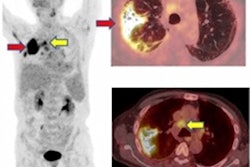

Participants underwent cardiopulmonary F-18 FDG PET/MRI and DECT imaging of the lungs. For comparison, the group also imaged a control group that included subjects with severe acute COVID-19 infection but without cardiopulmonary symptoms.

According to the results, PET/MRI scans were abnormal for 52 (57%) of the subjects: 22 showed cardiac involvement suggestive of myocarditis, 20 presented uptake reminiscent of pericarditis, 10 showed periannular uptake, and 28 showed vascular uptake (aortic or pulmonary). DECT revealed abnormalities in 63 (90%) of the subjects, with 47 demonstrating pulmonary infiltrates and 41 abnormal perfusion.

There was no myocardial, pericardial, periannular, or pulmonary uptake on the PET/MRI scans of the control group.